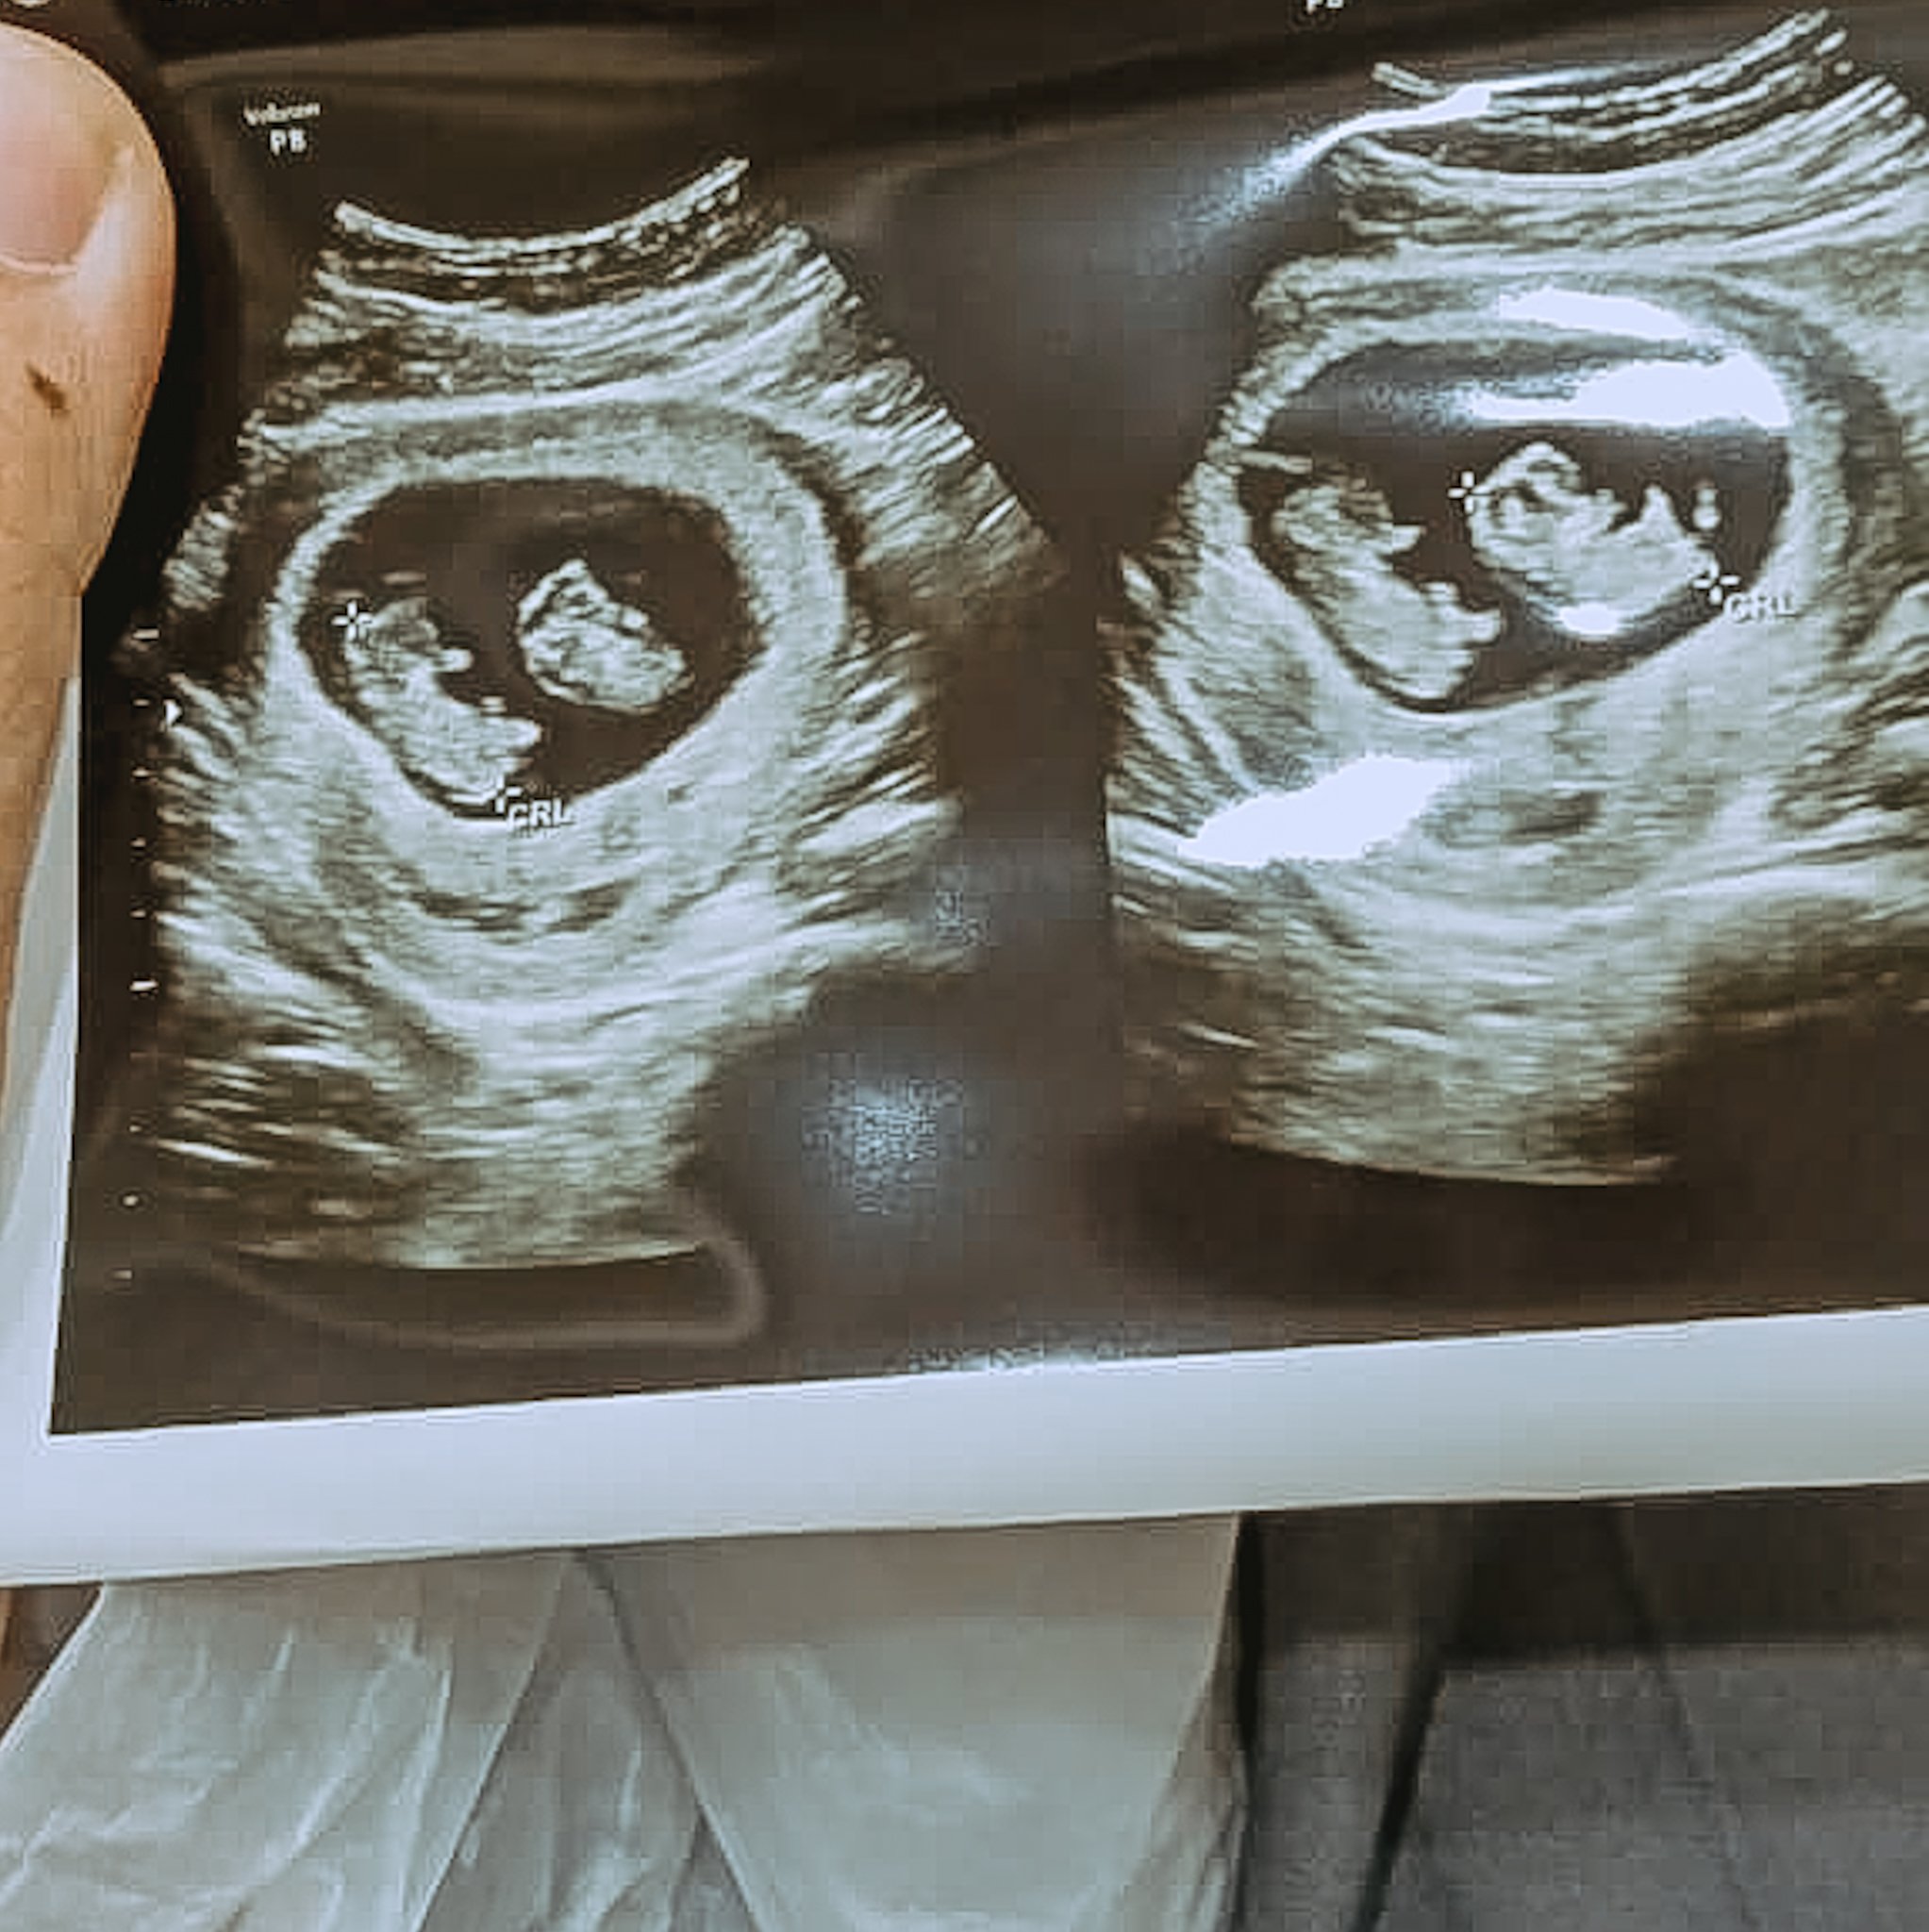

“Oh, pantes aja mual-mual terus. Bayinya dua!” kata dr. Retno yang sontak membuat kedua mata kami terbelalak. Kami lalu berkaca-kaca, terharu bahagia. “Karena bayinya gemeli (kembar), jadi lahirannya harus caesar di rumah sakit ya,” dokter berkacamata itu melanjutkan.

Seiring dengan bertambahnya usia kandungan Ara, terlihat bahwa salah satu bayi berada di posisi melintang (sungsang) di area antara perut dan dada. Kondisi ini semakin memastikan persalinan Ara harus dijalani dengan operasi caesar. Pada dasarnya, bayi kembar—meski dua-duanya posisinya normal sekalipun—memang sebaiknya dilahirkan secara caesar.